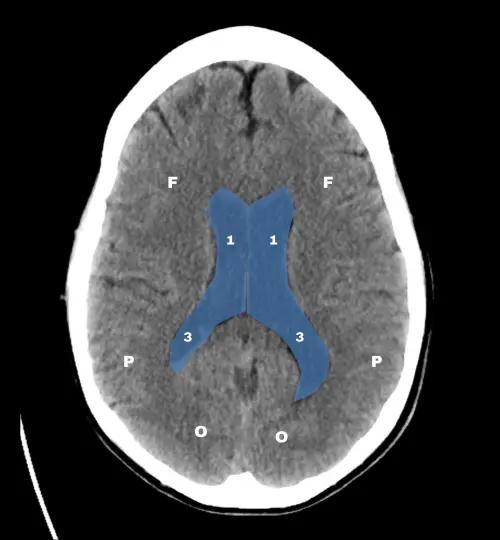

El doctor James Smirniotopoulos, neuroradiólogo y profesor universitario, propuso que bastaba con reconocer tres cortes axiales estratégicos para tener una idea global de la anatomía cerebral en la TC.

Los tres niveles clave son: el tronco encefálico, los ganglios basales y los ventrículos laterales. Una vez dominados, resulta mucho más sencillo interpretar variaciones y detectar alteraciones.

Por último, en el corte de los ventrículos laterales, conviene reconocer el septum pellucidum, la línea media y el cuerpo del núcleo caudado.

Estos elementos son puntos de referencia para evaluar tanto la anatomía normal como desplazamientos o efectos de masa.